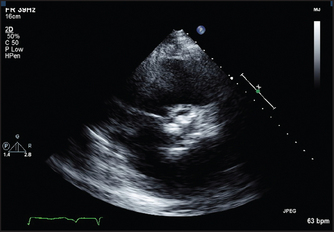

7. Hypertrophic cardiomyopathy. Certain anatomical abnormalities are characteristic of this condition (see Figure 8.21). There is asymmetrical septal hypertrophy (ASH). The normal interventricular septum measures up to 11 mm in thickness. This may be considerably increased to 40 mm or even more. Doppler interrogation may reveal a gradient in the left ventricular outflow tract or mitral regurgitation, or both.

Figure 8.21 (a) and (b) Hypertrophic cardiomyopathy (From Baker T, Nikoli

G, O’Connor S, Practical cardiology, 2nd edn. Sydney: Churchill Livingstone, 2008, with permission.) Churchill Livingstone